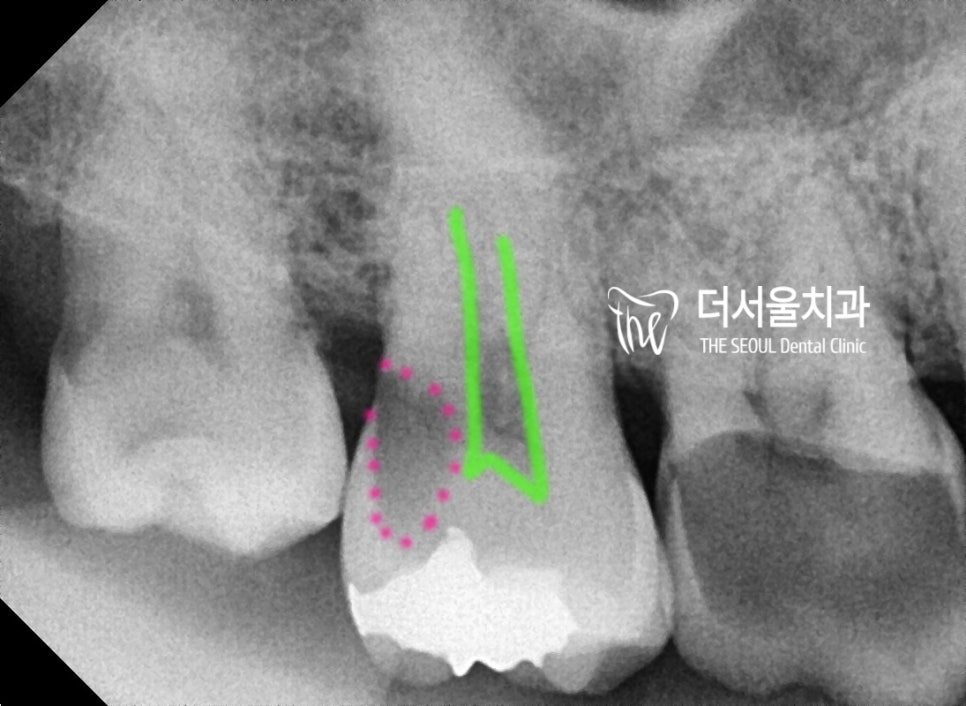

방사선 사진을 보면, #10번대의

어금니 2개에 문제가 있음을 알 수 있습니다.

구강 내 사진에서는

제 1대구치의 교합면의 1/4 가량이

치아 우식증에 따라서 파절 되어있는 것을

보실 수 있습니다.

제 2대구치는 아래에서 설명드릴텐데,

사랑니와 붙어있는 인접면에 광범위

우식증이 발생되어 있는 상태입니다.

그리고, 맨 뒤에 있는 사랑니는 발치 예정입니다.

충치의 입구는 좁지만,

안으로 들어갈 수록 커지는 형태의

전형적 proximal caries (인접면 충치)의

형태를 볼 수 있습니다.

초록색으로 표시를 해 둔 곳은

치수(신경이 있는곳)인데 충치와 거리가

꽤나 가깝죠?

그래서 제 1대구치와 제 2대구치는

신경치료를 진행해야 되는데

제 1대구치의 경우에는, 남아있는

치관이 거의 없기 때문에 레진코어

과정을 거쳐야 되는 상황입니다.